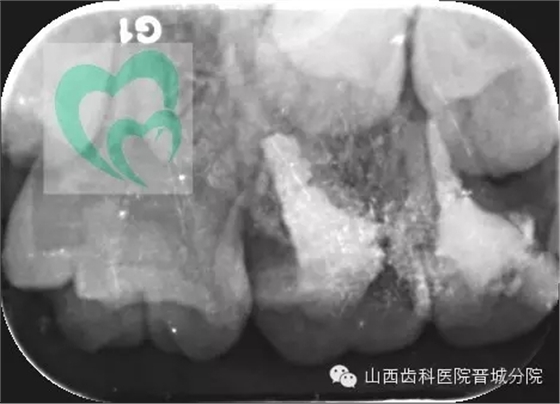

下面展示一例由我院龐超醫(yī)生操作并整理資料的兒童乳牙預(yù)成冠病例。

一個月后復(fù)診的樣子,沒有任何不適,棒棒噠!